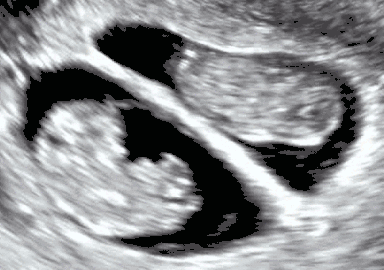

موجات فوق صوتية على البطن لتوائم أحادية الكيس السلوي في عمر حملي 15 أسبوعا. ولا يوجد أي علامة على وجود أي غشاء بين الأجنة. ويظهر التوأم في اليسار في المستوى الإكليلي، بينما تظهر أجزاء من الصدر العلوي والرأس من التوأم في اليمين في المستوى السهمي.